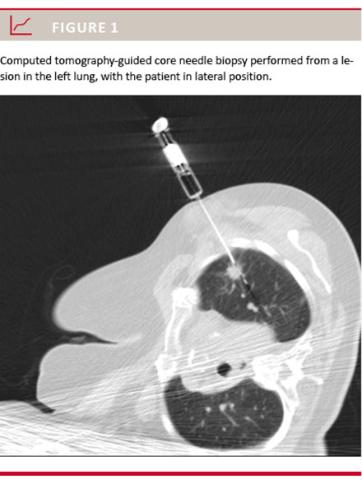

We used non-coaxial technique. The core needle biopsies were performed with an 18-gauge core needle (Angiotech, Stenløse, Denmark) (Figure 1). The tissue samples were placed on sterile millipore paper and sent for histological examination in a formalin suspension. The fine-needle aspirations were performed with a 0.8

The complication rate and the need for treatment were clearly higher among smokers and former smokers than among never-smokers. Only 13% of the never-smokers developed a pneumothorax compared with approximately 30% in the group of smokers and former smokers. Every fourth patient among the never-smokers required chest drainage, while this was the case in approximately every second patient in the group of smokers or former smokers. We found an increased risk of developing a pneumothorax when the patient was biopsied in a lateral position, p < 0.001 (Table 3), (Figure 1). This may be due to the increased lung movement that occurs in this position. In a prone position, there is less lung movement. We found a significantly increased risk for developing a pneumothorax when the biopsy was obtaied 5-10 cm from the skin surface as compared with when it was obtained less than 5 cm from the skin surface (Table 3). There was also a higher risk of developing a pneumothorax when the lesions were less than 1 cm in diameter (Table 3). We found that every fourth male and every third female developed a pneumothorax. Haemoptysis was also more common in females than in males (Table 3).